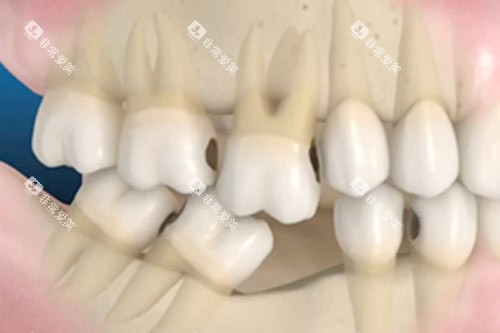

尽管在灵溪镇的出名度稍逊于牙贝恩,但牙美口腔凭借“种植牙长期质保”的约定,在本地中老年群体中口碑炸裂。该机构主打韩国登腾、瑞士ITI、瑞典诺贝尔等进口种植系统,所有种植体均提供电子质保卡,支持国境内联保。更贴心的是,术后5年内种植体周围炎治疗、基台螺丝松动调整等项目均免费,让患者无后顾之忧。

在技术层面,牙美口腔的“即刻负重”技术堪称一绝。通过智能化导板精细定位,能实现种植体植入后立即安装临时牙冠,当天即可进食软食。2025年4月,一位72岁患者在牙美完成全口种植后,当场啃起了苹果,视频在本地朋友圈疯传,引发热议。